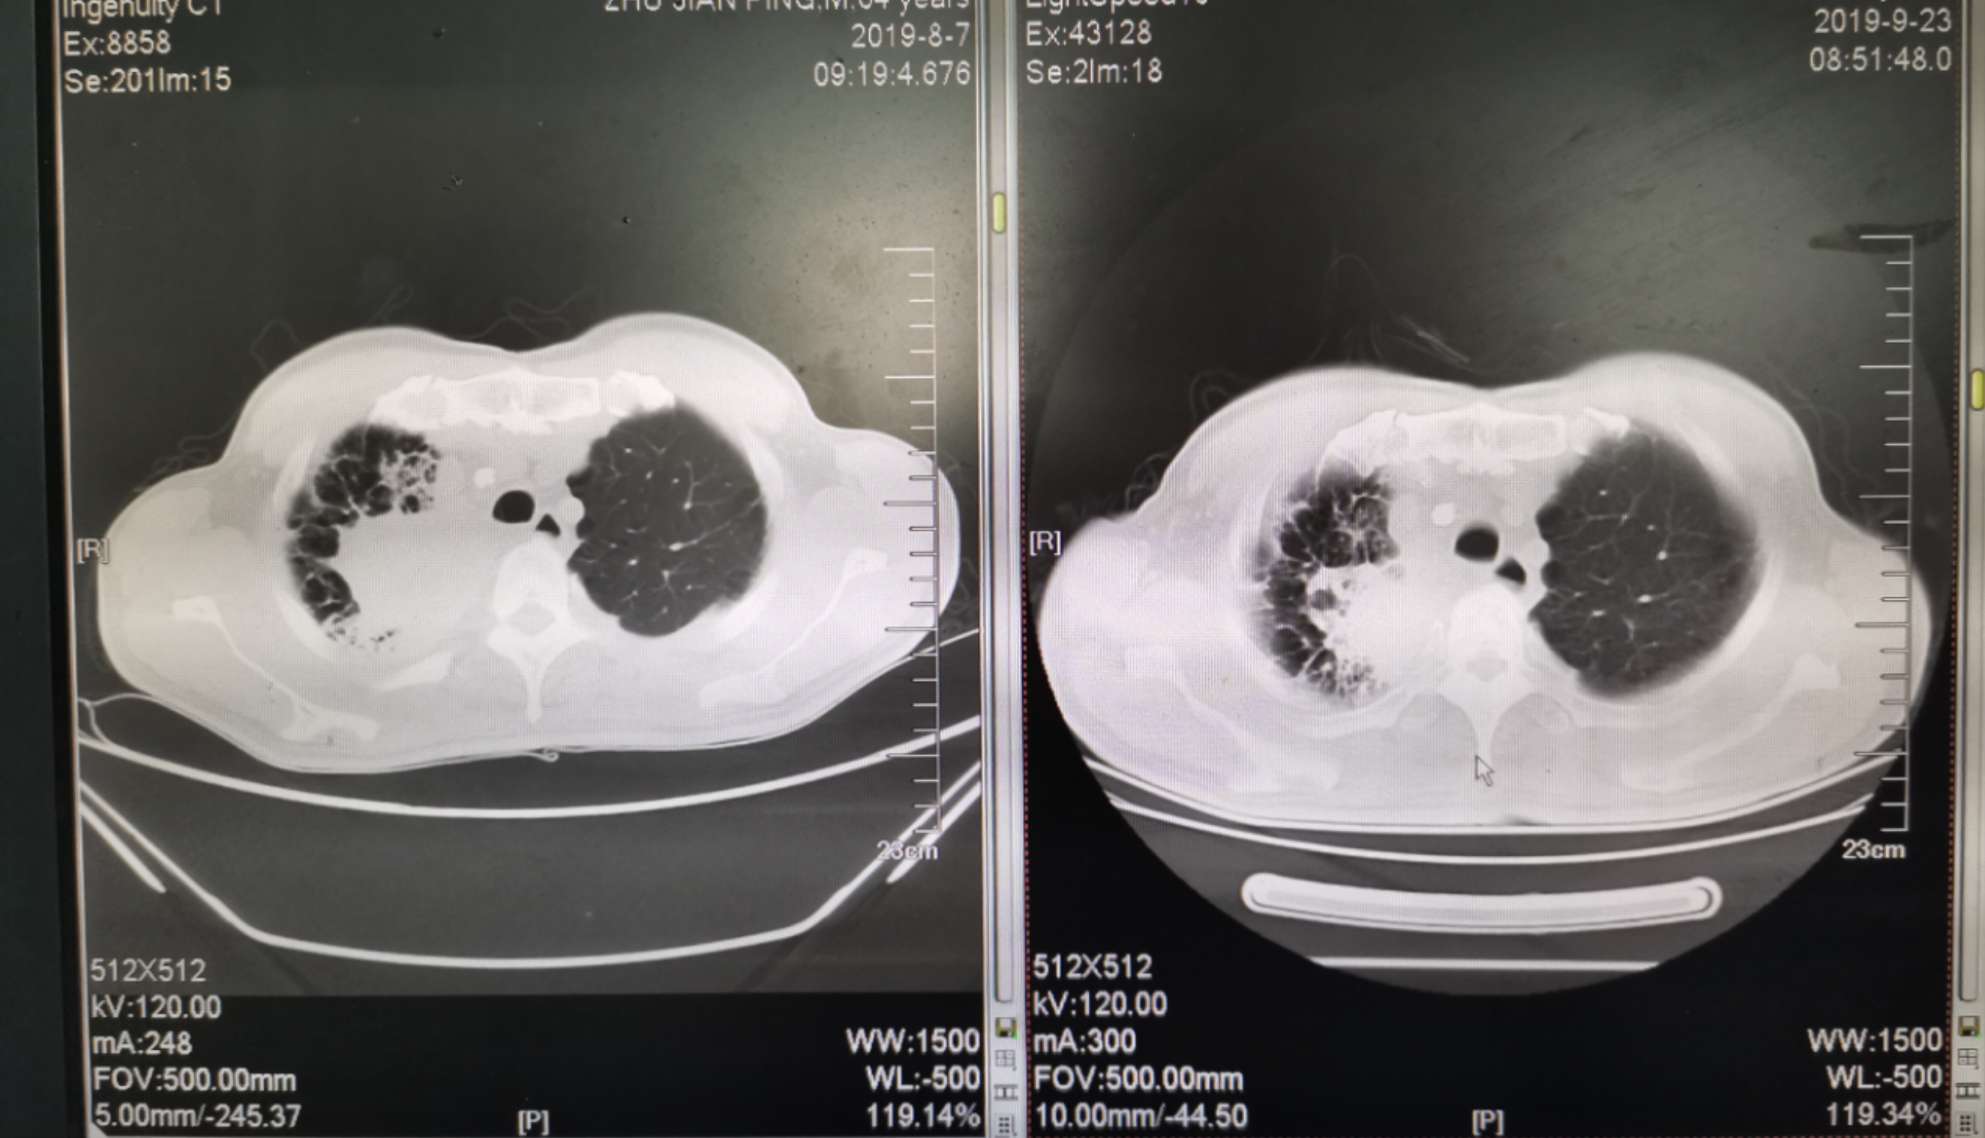

二化联合一k后复查ct对比

左边是上月化疗前的,右边是昨天拍的,今天上了第二次k药,准备明天第三期化疗。

我自己对着拍的,切面对的不是很准确,但大致上看的出来明显小了。